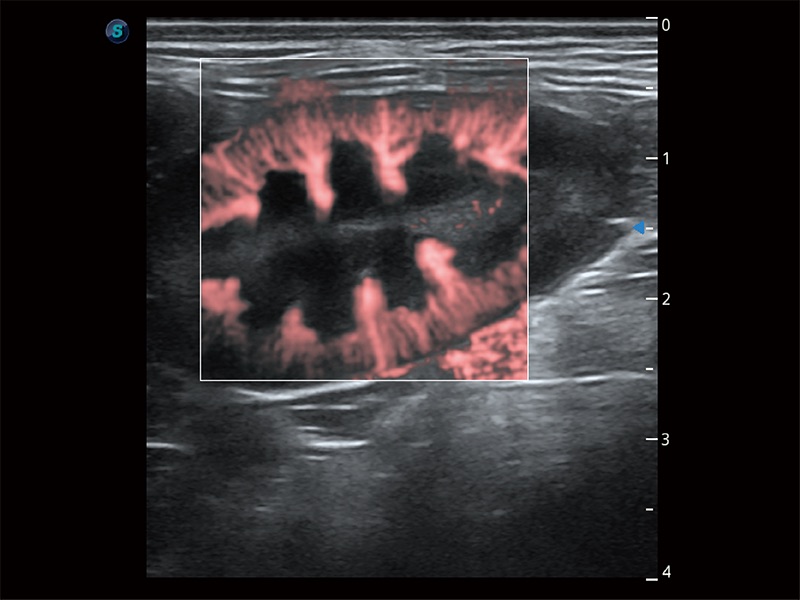

操作简便,无需高频度外力作用即可真实反映组织的形变,快速评估肿瘤良恶性。

为精细结构及组织边缘提供高清晰度的图像和更大的成像视野。帮助减轻医生的用眼疲劳,快速精准获得测量的数据。